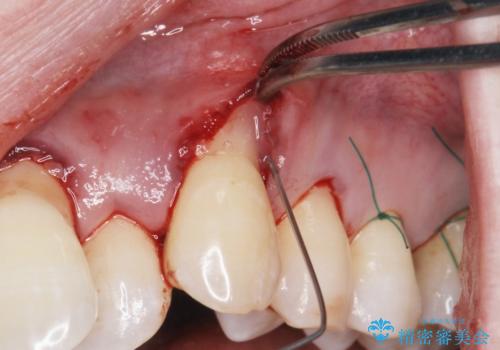

プラークコントロールが十分に行えるようになったのち、結合組織移植を用いた根面被覆手術を行います。

手術は静脈内麻酔下で行いほとんど記憶もない状態で終えることができます。

良好な結果が得られ、大変満足いただくことができました。